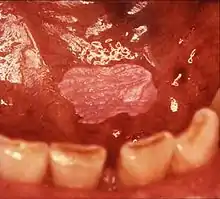

Leukoplakia on the inside of the cheek